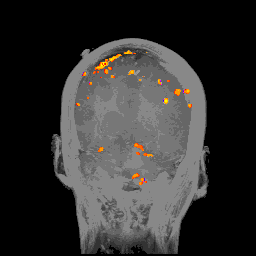

fMRI使用磁振造影追踪血液流动的变化。为什么要这么做呢?因为当大脑的特定部位变得活跃的时候,那个部位就需要更多的能量,也就需要更多的氧气,所以那些部位的血流会增加来传递更多的氧气。fMRI的扫描是这样的:

当然,大脑的各处时刻都有血液流过,这张图显示的是血流增加的部分(红橙黄)和减少的部分(蓝)。因为fMRI扫描的是整个大脑,所以结果是3D的。

fMRI有很多医学应用,比如告知医生病人中风后脑的各个部位是否运行正常。它也教会了神经科学家很多东西,包括大脑的哪些区域参于哪些功能。fMRI扫描也能帮助提供整脑在给定时刻的整体情况,并且很安全,而且完全无创。